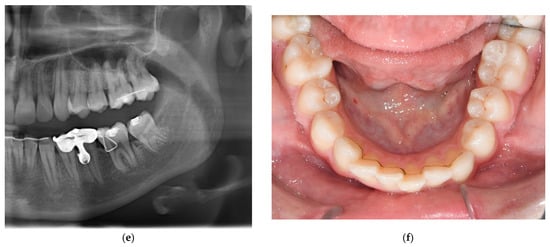

2. Diagnosis

3.3. Treatment Progress